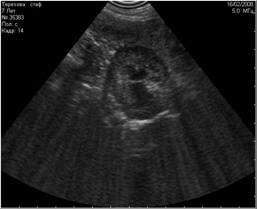

Рис1. Помехи, вызванные включённым рядом с аппаратом УЗИ сотовым телефоном. Во избежание этого лучше просить владельца выключать сотовый телефон при проведении ультразвукового исследования. |